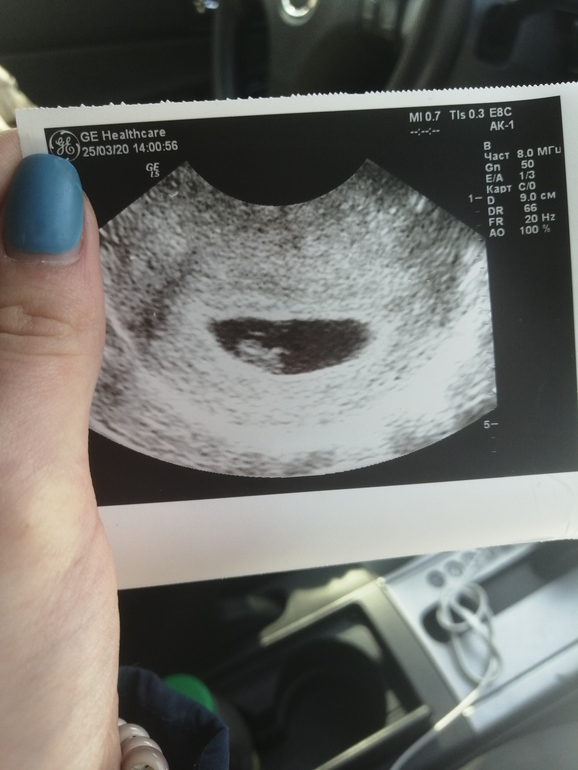

Второе УЗИ ❤️ 7+2

По животу опять не удалось врачу нас увидеть, по началу немного испугалась, но трансвагинально всё нашли ❤️

По М нам сегодня 7+2, по УЗИ ровно 7 неделек, КТР 9,3мм и СБ+

На УЗИ видела как бьётся сердечко и это так трогательно 😭🤤 отправили расти и сказали приходить уже на скрининг на 11 недельке. Завтра уже иду становится на учёт )